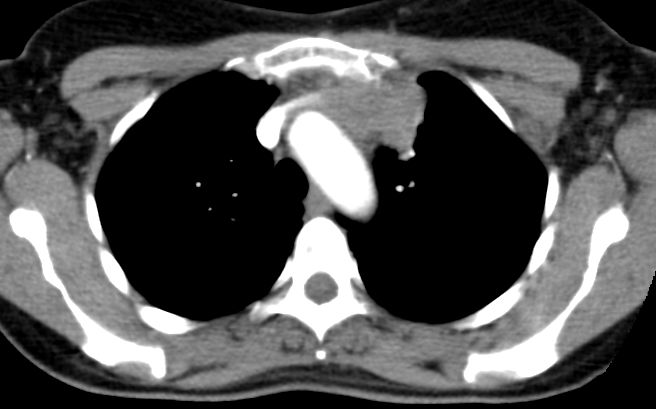

Infiltration der angrenzenden Lunge. Das Referenzzentrum hat das Stadium trotzdem bei II belassen.![]() |